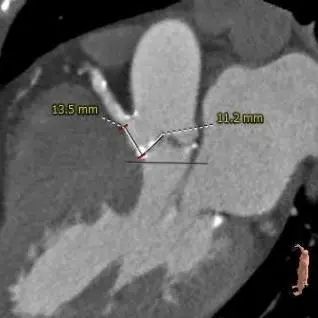

主动脉根部测量

冠脉高度、瓣叶长度测量

瓣环上多平面测量